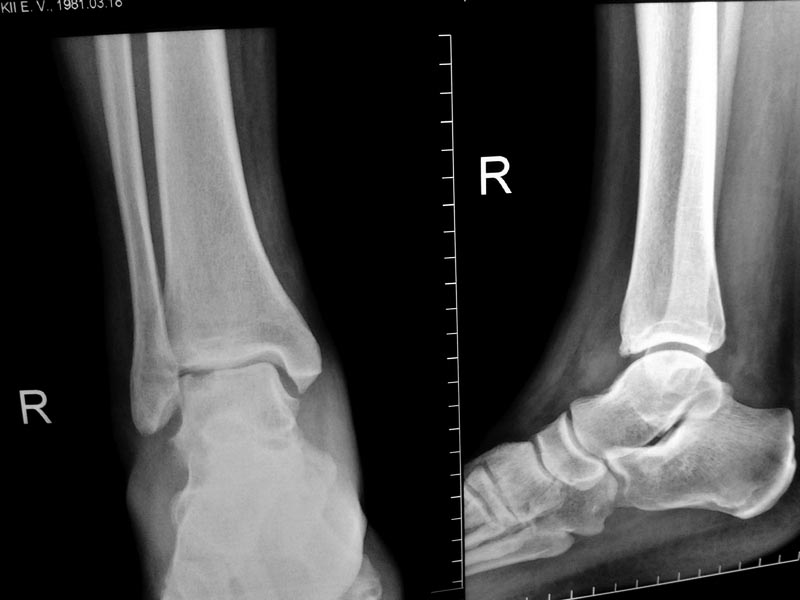

У 40-летнего мужчины около 3 месяцев появляются боли и отек в правом голеностопном

суставе.Травмы, перегрузки, спорт и вредные привычки отрицает. На Рграммах 2 месячной

давности патология стопы не видна\качество снимков низкое\ На свежих снимках виден

глубокий некроз блока тарана.Отек, хромота и боли стихают после терапии НПВП. Выбираем